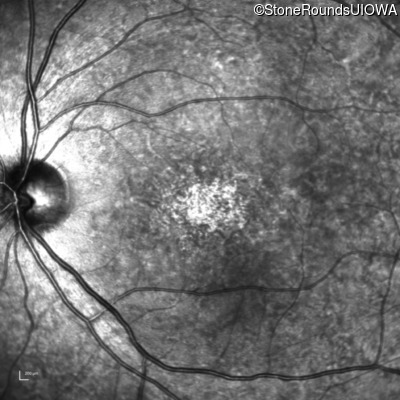

The clinical features favoring the diagnosis of ABCA4-associated autosomal recessive Stargardt disease in this patient include: loss of acuity at the beginning of the second decade, parafoveal photoreceptor loss on OCT, pisciform flecks in the macula with clear peripapillary sparing, and normally sighted parents.

All three of the cardinal ophthalmic features of Mendelian macular dystrophies are present in this patient. The most striking features of the fundus exam are the numerous yellow flecks at the level of the RPE. Flecks are most commonly seen in AR Stargardt disease and pattern dystrophy although they may be seen in some of the rarer Mendelian maculopathies as well. The visual acuity in patients with AR Stargardt disease is often "worse than the fundus looks" while the acuity in pattern dystrophy is often quite good despite extensive flecks. The pedigree of this patient is compatible with ABCA4-associated Stargardt disease and the better than expected acuity is attributable to foveal sparing (see below). The onset of reduced acuity at age 10 is much more characteristic of ABCA4 disease than pattern dystrophy. Another feature present in this patient that is very frequently seen in Stargardt disease is peripapillary sparing. However, this sign can be seen in pattern dystrophy as well. When central atrophy is present in ABCA4-associated Stargardt disease it often somewhat shiny (which is uncommon with the geographic atrophy of pattern dystrophy or age-related macular degeneration). Some patients with ABCA4-associated Stargardt disease can have some preservation of the fovea giving a zonal "bullseye" appearance to the center of the macula. Sometimes this preservation is associated with preserved acuity as in this case. The outer nuclear layer (ONL) is much thinner than normal on OCT, indicative of photoreceptor loss. This is associated with a thinning of the ellipsoid zone which is usually many times brighter and thicker than the external limiting membrane (ELM). These two lines are essentially equal in intensity in this patient. The foveal sparing is seen on OCT only as a small bit of retinal convexity in the center of the atrophy coupled with a small bit of residual RPE flanked by bare Bruch's membrane. The presence of a robust I2e isopter on Goldmann perimetry places this patient in the least severe half of all Stargardt patients (see Schindler, et al., 2010). Most patients with ABCA4-associated disease are somewhat myopic as is this patient. Stargardt patients also tend to perform very poorly on pseudoisochromatic plates, even when their acuity is still fairly good as it is here.